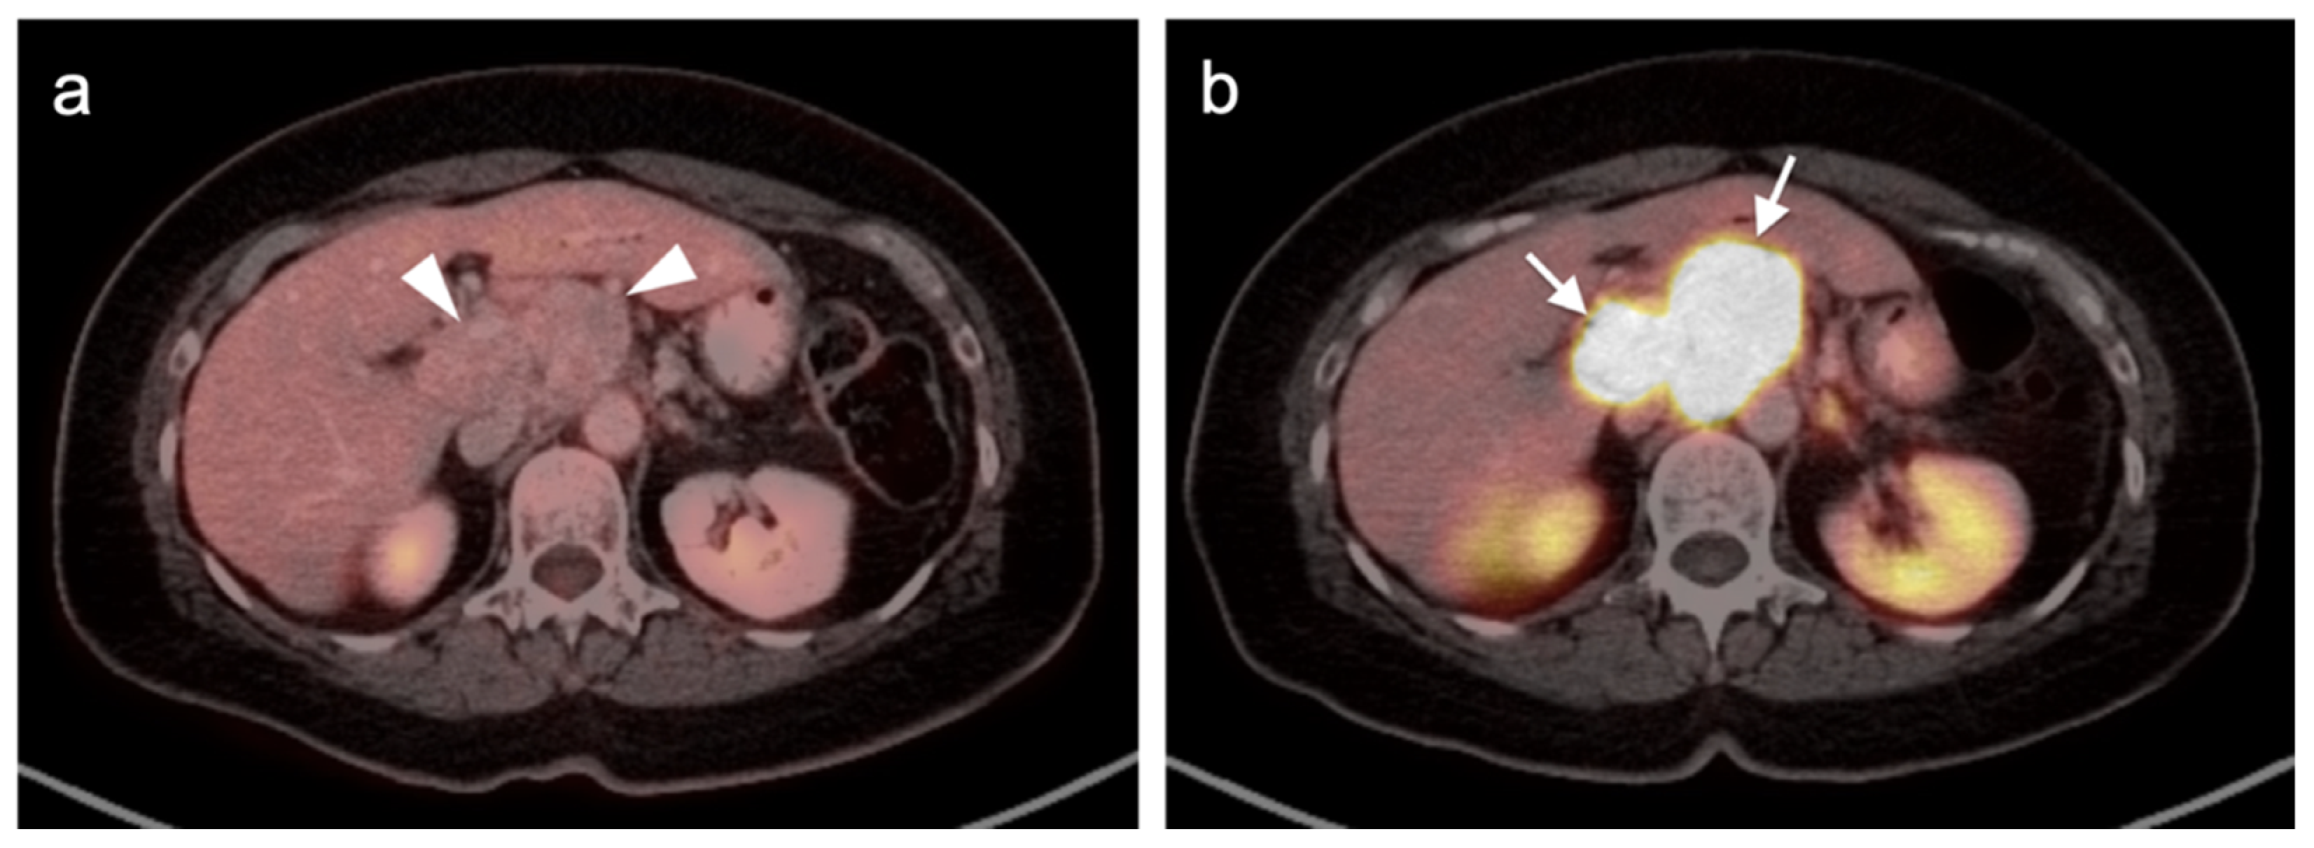

4.4. Bronchial Carcinoid